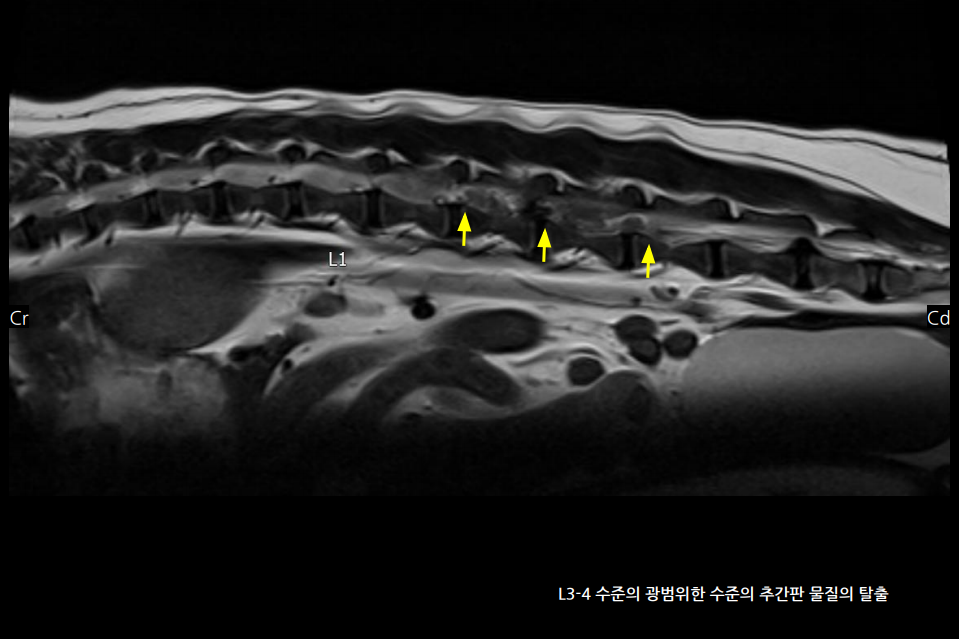

MRI 상 요추 3-4번 사이에 50% 이상의 심한 디스크 물질의 척수 압박이 확인되었고, 수술적인 제거가 진행되었습니다.